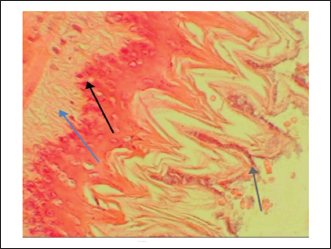

The gastric tissue slides were examined under a microscope for morphological changes such as hyperemia, hemorrhage, edema, necrosis, inflammatory changes, distortion, erosion, and ulcers caused by the destructive effects of indomethacin on stomach tissues. No pathological changes were observed in the normal control group (Fig. 1). Rats in the ulcer control group showed significant damage to the surface epithelium, necrotic areas penetrating the mucosal layer, and severe edema of the submucosal layer. Additionally, there was congestion with infiltration of inflammatory cells (Fig. 2). Histological results revealed that the treated rats with ranitidine had less protection of the gastric lining due to mild infiltration of leucocyte and edema in the submucosal layer, in addition to less disruption in both the superficial and deep mucosal layers. Treatment doses (300, 400 and 500 mg/kg) with P. farcta extract. Groups treated with P. farcta extract (300 and 400 mg/ kg) showed mild infiltration of inflammatory cells, edema, or significant disruption of the deep mucosa (Figs 5 and 6) while, P. farcta extract group (500mg/ kg) prevented histological changes and showed no infiltration of inflammatory cells, edema, or significant disruption of the deep mucosa (Figs 3, 4 and 7).

Fig. 3. Ulcer control group damage (↗) to the epithelium, necrotic areas penetrating the mucosal layer, and (↗) severe edema of the sub-mucosal layer with congestion and (↗) infiltration of inflammatory cells